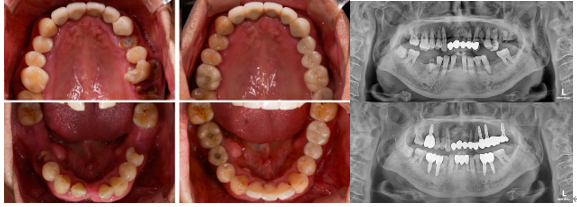

インプラント

【治療ケース】

【担当医からのポイント】この 患者様は来院時、複数の部位に虫歯が進行しており、歯がたくさん抜けている状態でしたので、全体の歯並びと噛み合わせが大きく乱れていました。歯が抜けたまま時間が経過し、隣の歯が傾いたり、噛み合わせが崩れる変化が現れていました。

診断の結果、歯根だけが残っている、または虫歯がひどく残すのが難しい歯、歯周病が進行した歯、突き出過ぎて噛み合わせの妨げになっている歯は整理し、インプラントによる治療方針を立てました。治療は部位ごとの状態に応じて分けて進め、左側は歯茎が回復した後にインプラントを埋入する方式(遅延埋入)、右側は抜歯と同時にインプラントを埋入する方式(即時埋入)を適用しました。

1次手術でインプラントが顎の骨に安定的に定着し、ヒーリングアバットメントをすぐに連結することができ、追加の手術なしに一度で完了することができました。現在はインプラントが良好に維持されるよう、定期的に検診を続けながら管理中です。